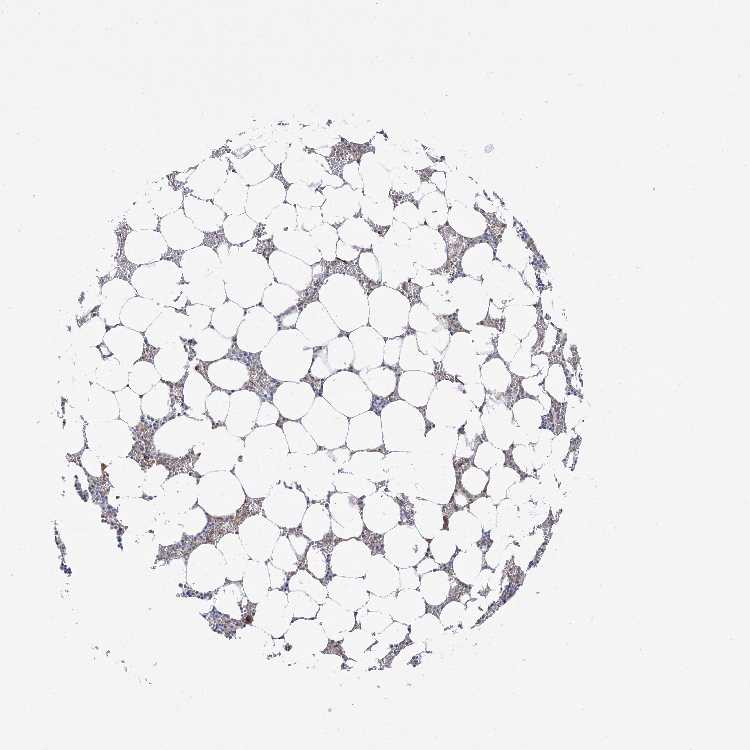

BONE MARROW - Antibody stainingi

Antibody staining in the annotated cell types in the current human tissue is reported as not detected, low, medium, or high, based on conventional immunohistochemistry profiling in selected tissues. This score is based on the combination of the staining intensity and fraction of stained cells.

Each image is clickable and will lead to virtual microscopy that enables deeper exploration of all samples and also displays staining intensity scores, fraction scores and subcellular localization as well as patient and tissue information for each sample.

Antibody HPA036698Antibody HPA036699

Hematopoietic cells LowLow